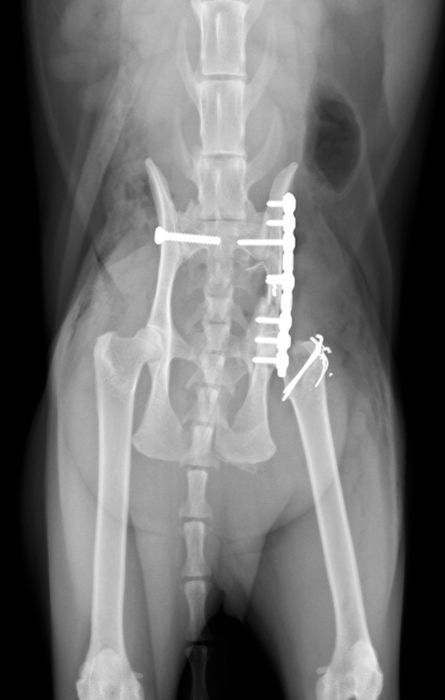

骨折治療について

動物も人間と同じように骨折や脱臼をします。

原因として交通事故などの大きな外力によるものもありますが、日本では小型犬が主体となっているため、ソファや抱っこしている所からの落下といった比較的小さな外力でも生じることが多くなっています。

骨折や脱臼の治療は、ギプスなどの処置のみで済むケースもありますが、ほとんどのケースは完全骨折や脱臼を生じますので、手術が必要となります。

当院における骨折治療は、動物のステータス、骨折の発生部位や分類などを考慮して「髄内ピン」「骨プレート」「創外固定器」を単独もしくは組み合わせて使用することで適当な固定力を得られるように施術しています。

●骨プレート

ステンレス製もしくはチタン製の金属の板(プレート)と骨ネジ(スクリュー)を使用して固定を行います。

●髄内ピンと骨プレートの併用(プレート-ロッド併用法)